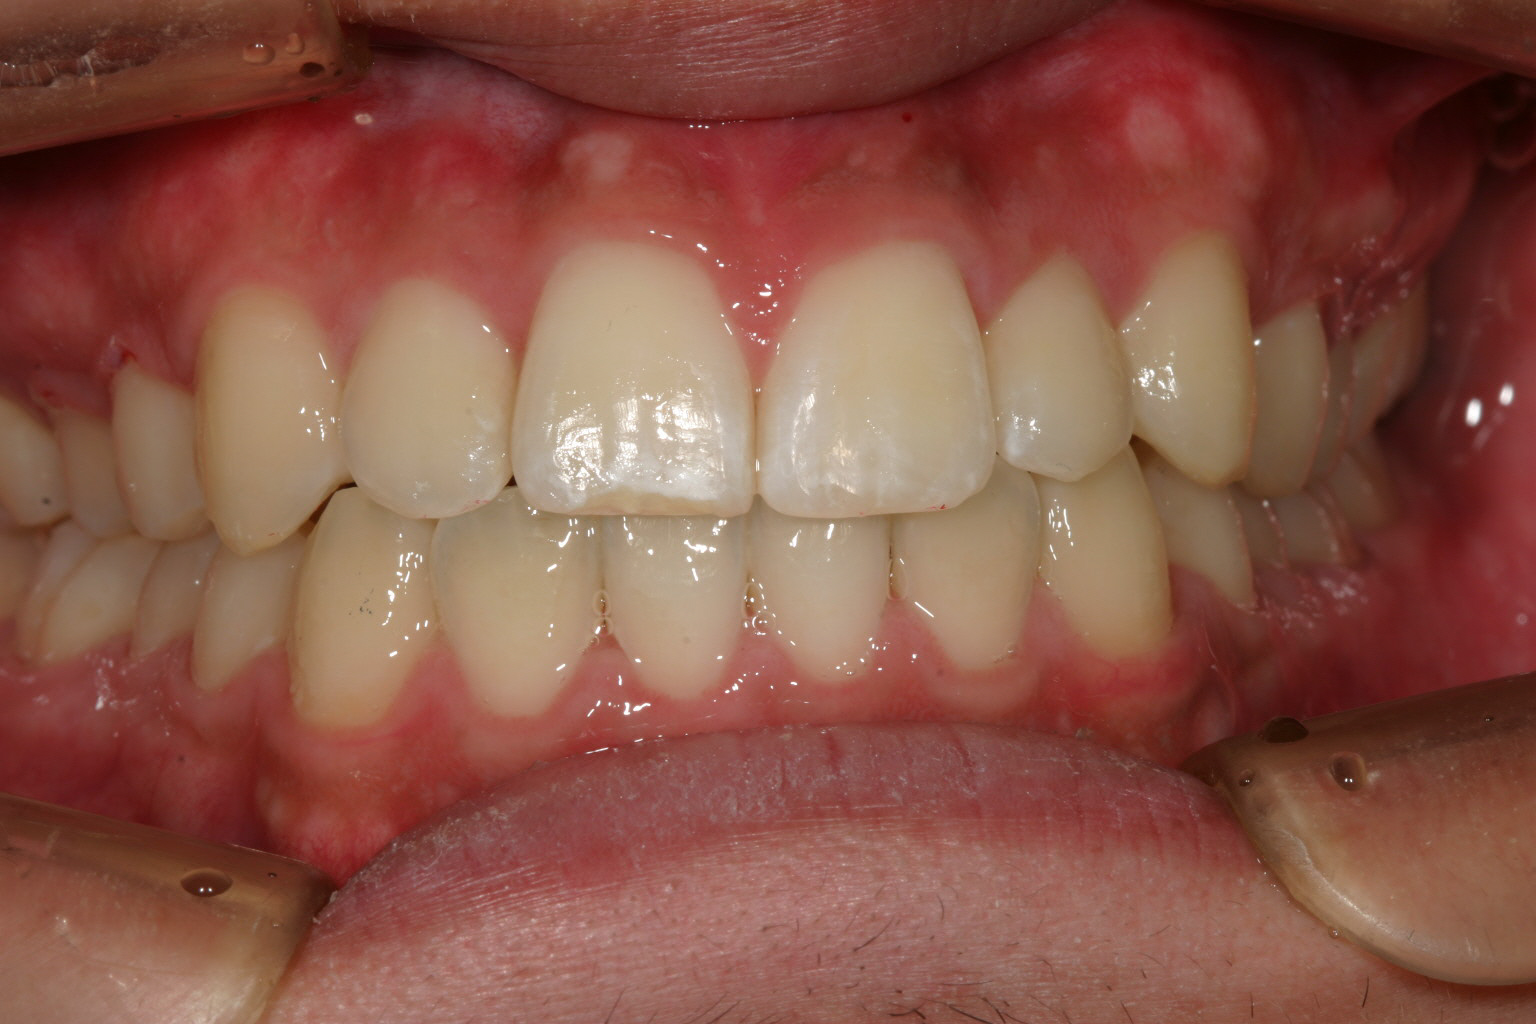

アーチを広げ綺麗に配列しました。

下顎も綺麗に改善しました。

オーバージェットも綺麗に改善しています。

と言う事で少しアーチを広げる事によりこの様に綺麗な咬み合わせに改善します。